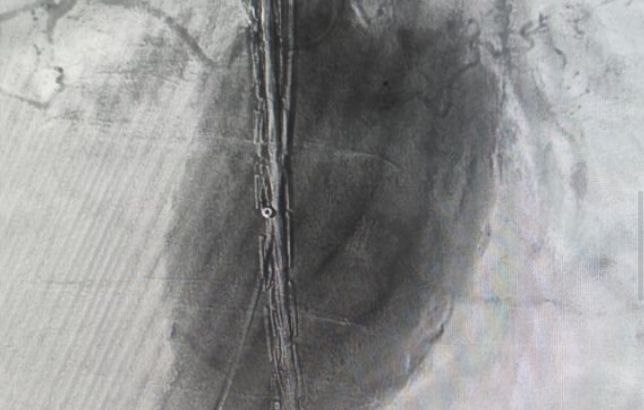

Фото: комитет здравоохранения Волгоградской области

Специалисты Волгоградской областной больницы № 1 успешно выполнили сложную эндоваскулярную операцию по установке стент-графта для лечения аневризмы брюшной аорты.

«Стент-графт представляет собой комбинацию стента (металлической или полимерной сетки, которая поддерживает стенку сосуда) и графта (тканевой или синтетической оболочки), который обеспечивает дополнительную прочность и защиту. Конструкция укрепляет стенку аорты изнутри, создавая новый прочный канал для кровотока», – прокомментировали в облздраве.

Таким образом удалось восстановить функцию магистрального сосуда и предотвратить опасные для жизни осложнения.